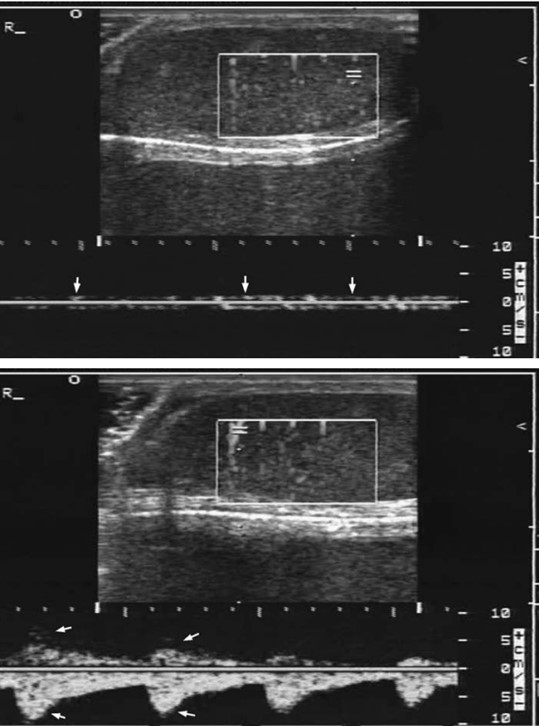

Figure 2. Examples of a normal testicular venous waveform (upper panel) and an arterial waveform (lower panel)10